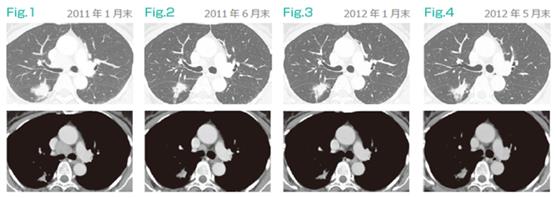

案例:60歲女性 無吸煙史 2011年1月診斷為T4N3M1a肺腺癌(肺內及鎖骨上淋巴結轉移)。2011年3月初開始CDDP+PEM+BV化療,并切除了右鎖骨上淋巴結,將切除淋巴結溶解制作DC疫苗,以待后用。至6月,CDDP+PEM+BV治療4次,細胞療法3次,發現腫瘤縮小(PR),隨機停止聯合化療,7月開始維持治療僅使用貝伐+細胞療法,觀察至2015年5月底腫瘤未進展。